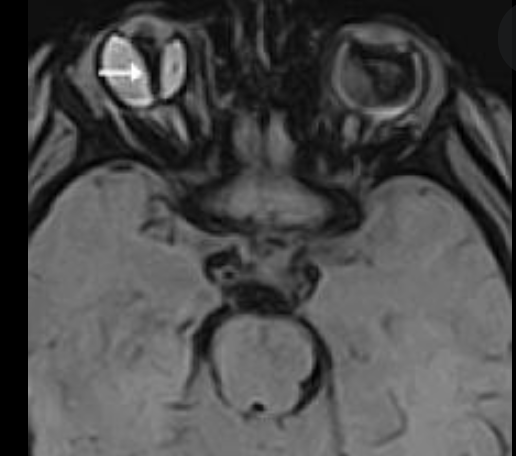

Buphthalmos

Buphthalmos: